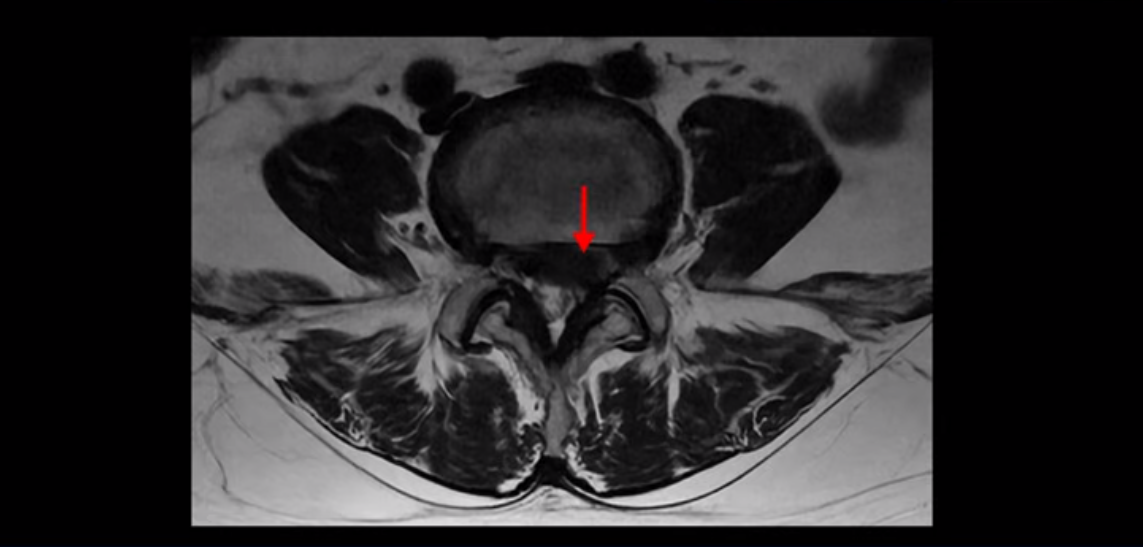

단면을 보면 디스크 수핵은 왼쪽으로 심하게 밀려 나와 있고

좌우 뒤쪽에는 황색 인대가 두꺼워져 있습니다.

앞에서는 디스크 수핵이 신경 공간으로 침범하고 뒤에서는 두꺼워진 인대가 신경 공간을 좁히고 있습니다.

이렇게 신경 공간이 좁아진 것을 협착이라고 합니다. 왼쪽으로 신경 구멍이 더 좁아져 있으니까 처음에는 왼쪽 엉덩이와 다리가 아팠는데 몇 년 동안 주사 맞으면서 버티다 보니까 오른쪽 다리까지 아프게 됩니다. 결국 양쪽 다리가 너무 아파서 5분 걷기도 힘들어지게 됩니다.

디스크 파열은 심해 보이나 신경 구멍이 좁아지는 협착증으로 보자면 저희 다른 치료 후기에 나오시는 협착증 환자분들의 MRI에 비해 신경 구멍은 넓은 편입니다. 그래서 신경이 정말 심하게 눌릴 때 나타나는 다리의 힘 빠짐 증상은 없었고 통증, 즉 아프다는 증상을 제일 심하게 호소하셨습니다.